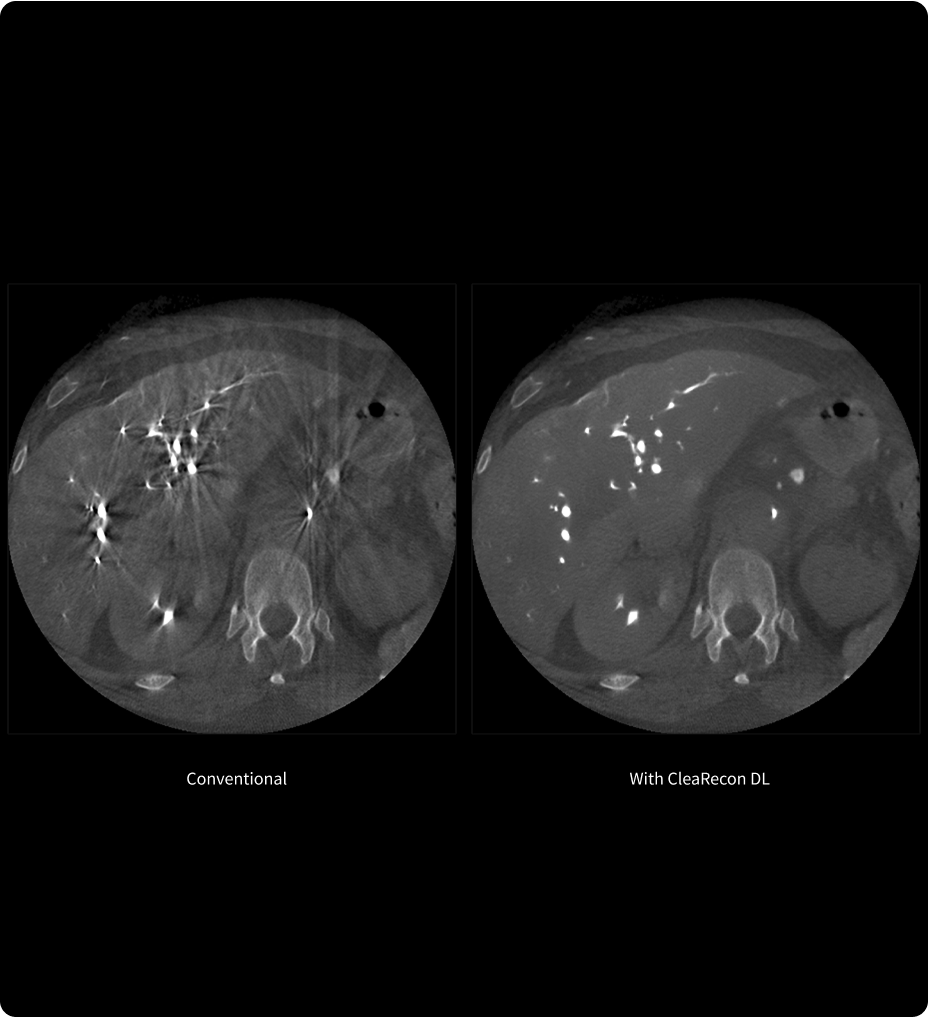

CleaRecon DL3,4

Entrez dans l’ère de l’IA,

accédez à une meilleure qualité d’image !

CleaRecon DL est une technologie de Deep Learning conçue pour améliorer la qualité des images de tomodensitométrie volumique à faisceau conique (CBCT) en éliminant les artéfacts en stries. Elle aide les cliniciens à obtenir des images plus nettes, améliorant ainsi leur confiance dans l’interprétation des images lors de l’analyse des données CBCT.

Il est essentiel de se sentir sûr de soi pour poser un diagnostic précis et planifier un traitement efficace.